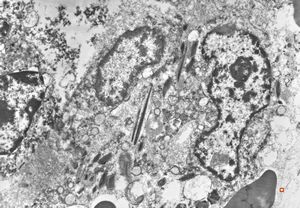

bone marrow - crystalloid inclusions Charcot-Leyden crystals formation

bone marrow - crystalloid inclusions Charcot-Leyden crystals formation v.s.